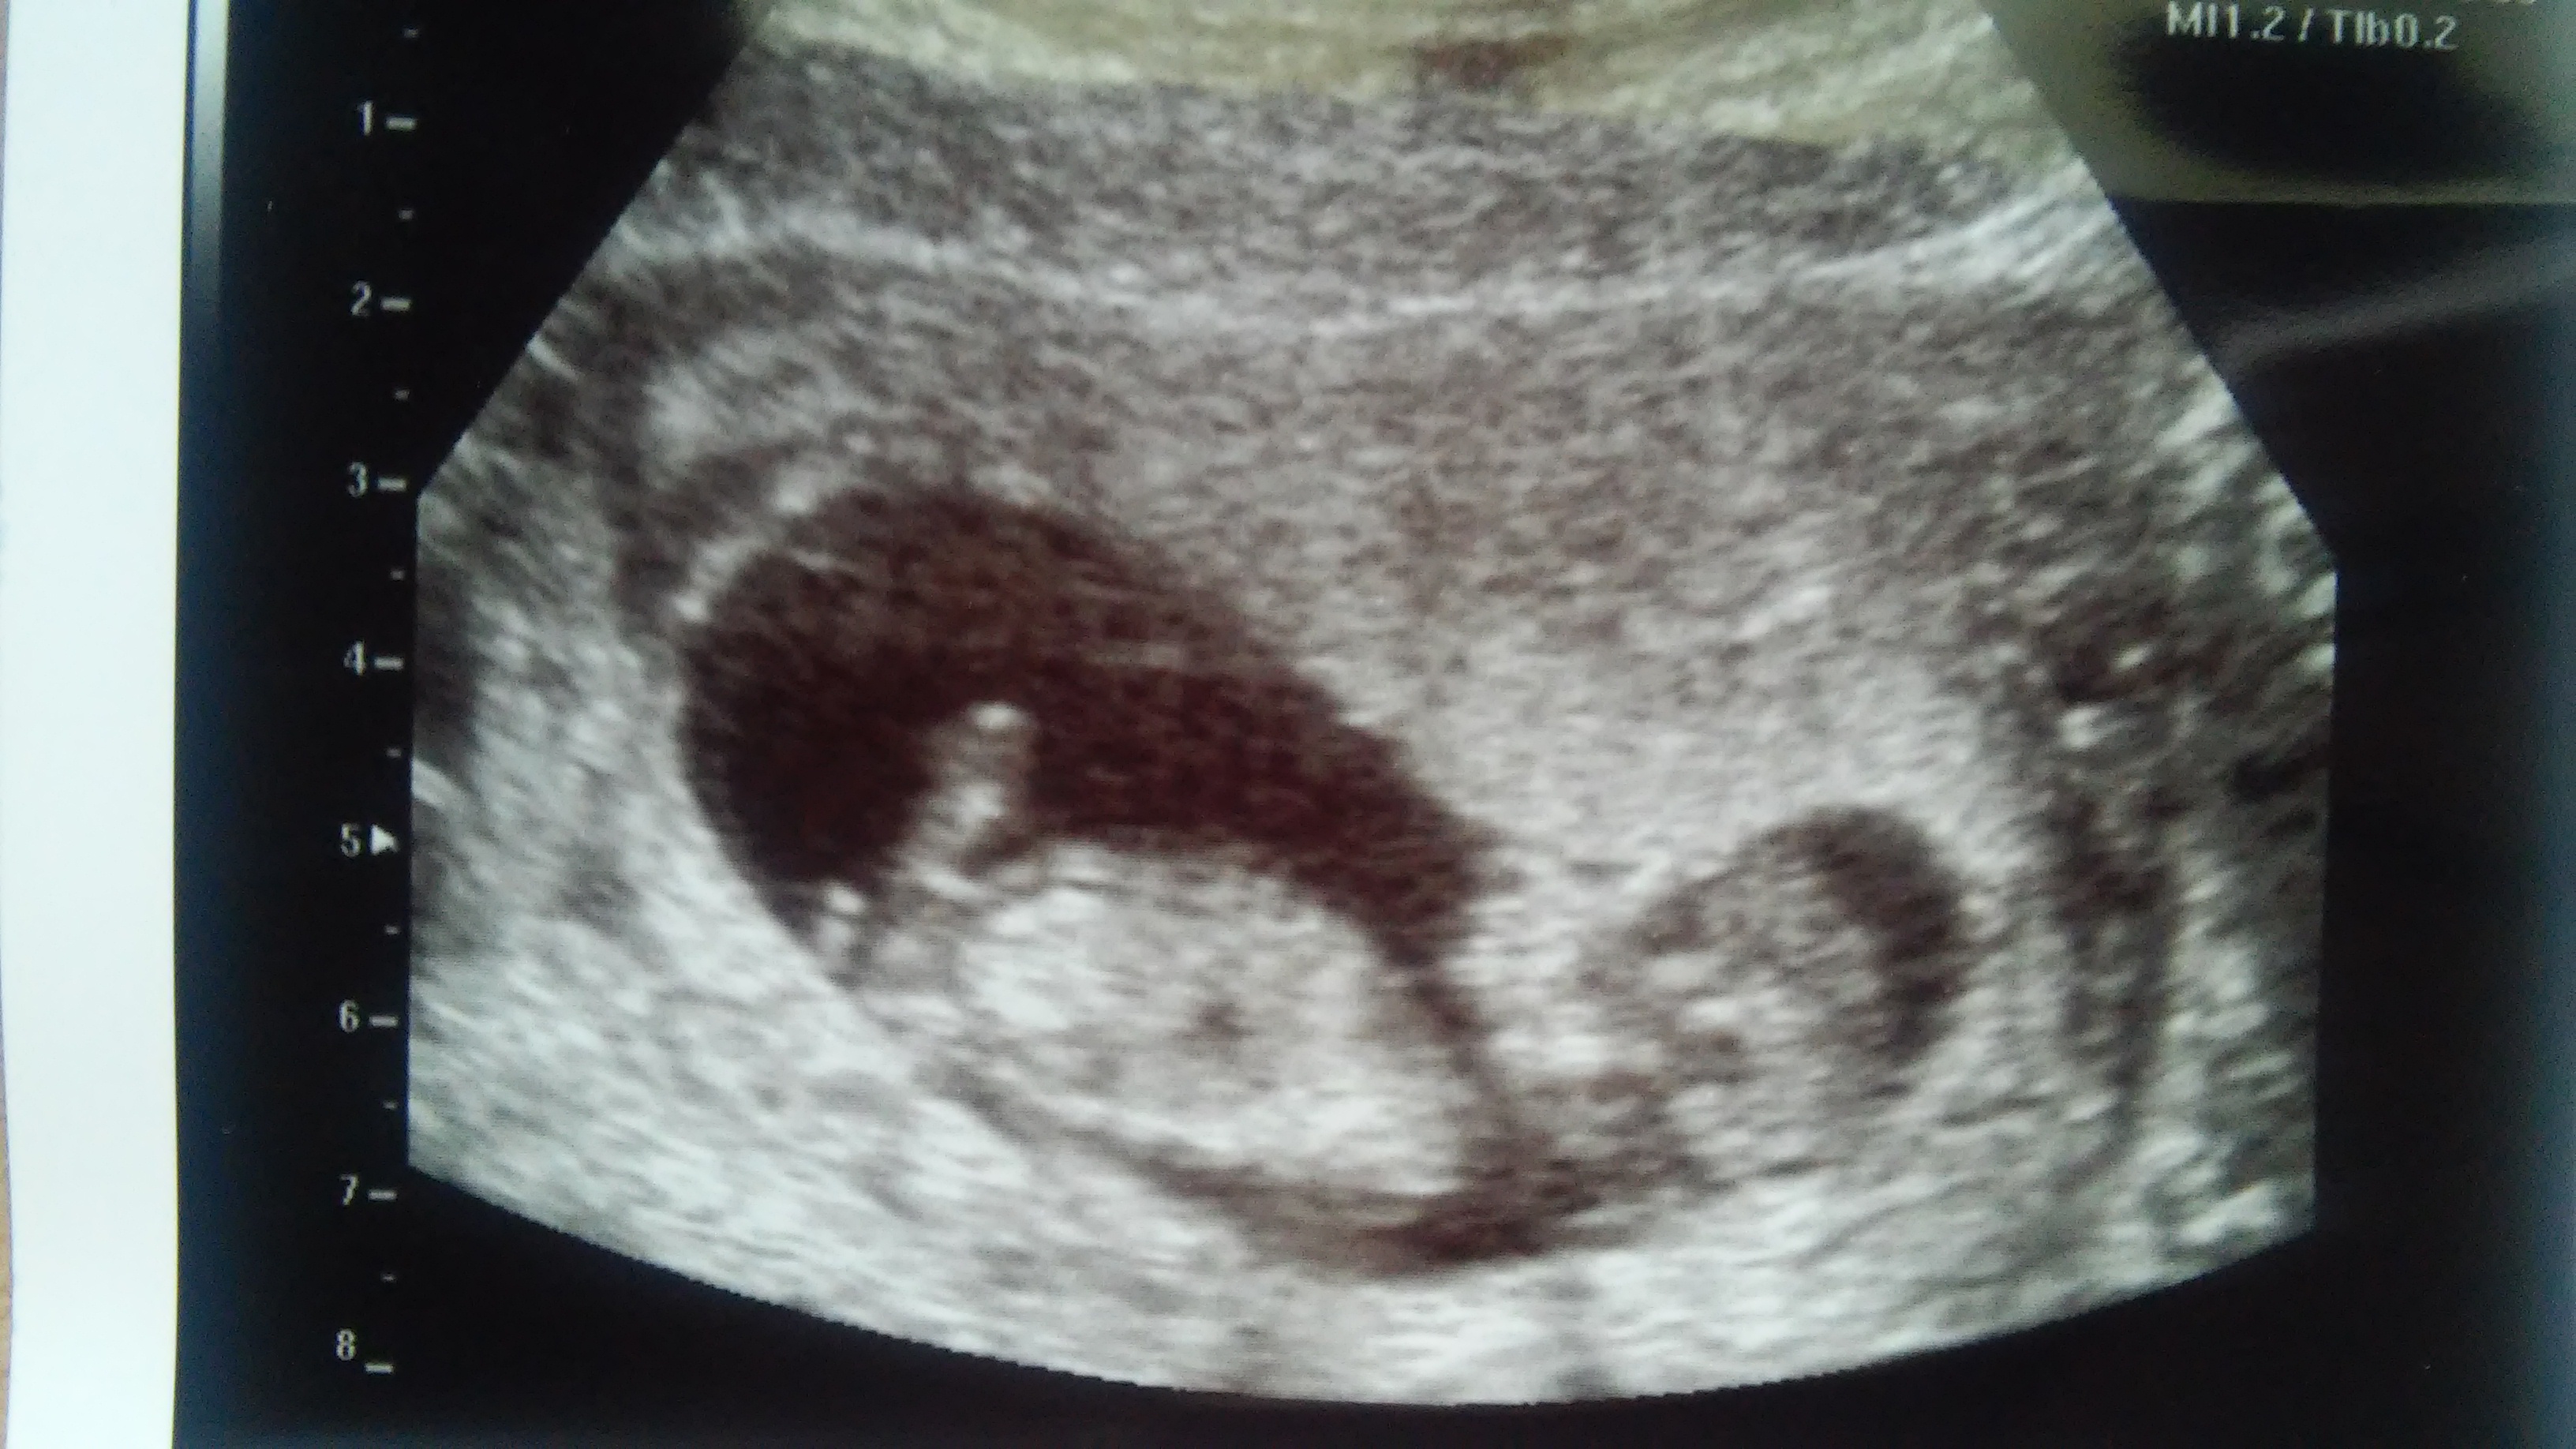

PLEASE help guessing gender.. boy or girl??? 12wks

Im am dying to know what i will have a boy or a girl! im 12 weeks and 2 days and had an ultrasound done today. PLEASE NOTE the umbilical cord was basically in the way the whole time thats the huge white thing in between the legs lol, so dont mistake that for something else :-)im hoping someone is able to look past the cord!! the ultra sound lady did gave me a picture of the butt, she placed an arrow next to it. they didnt want to give me a guess on the gender because theyre not allowed to with 12 weeks...

please help me figuring this out!! thank you so much!!Attachment 25235 Attachment 25236 Attachment 25237